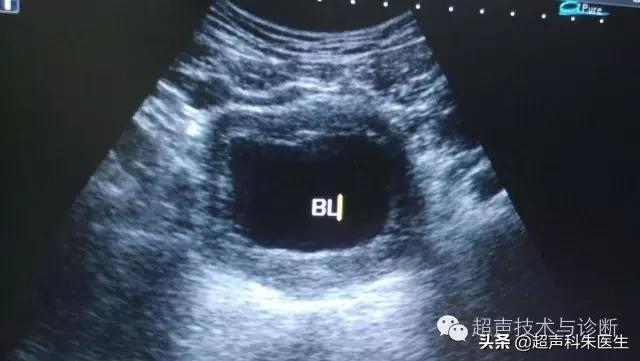

二、局部增厚型:声像图表现为膀胱内壁局限性增生呈团块状或结节肿瘤样增生突起,内部呈低回声,边界清楚,表面毛糙欠光整,基底部宽大且层次结构尚清晰,周围膀胱壁增厚。CDFI 和CDE于结节基底部可见呈点状及短棒状血流信号, 以静脉血流频谱为主,偶可见动脉血流频谱;